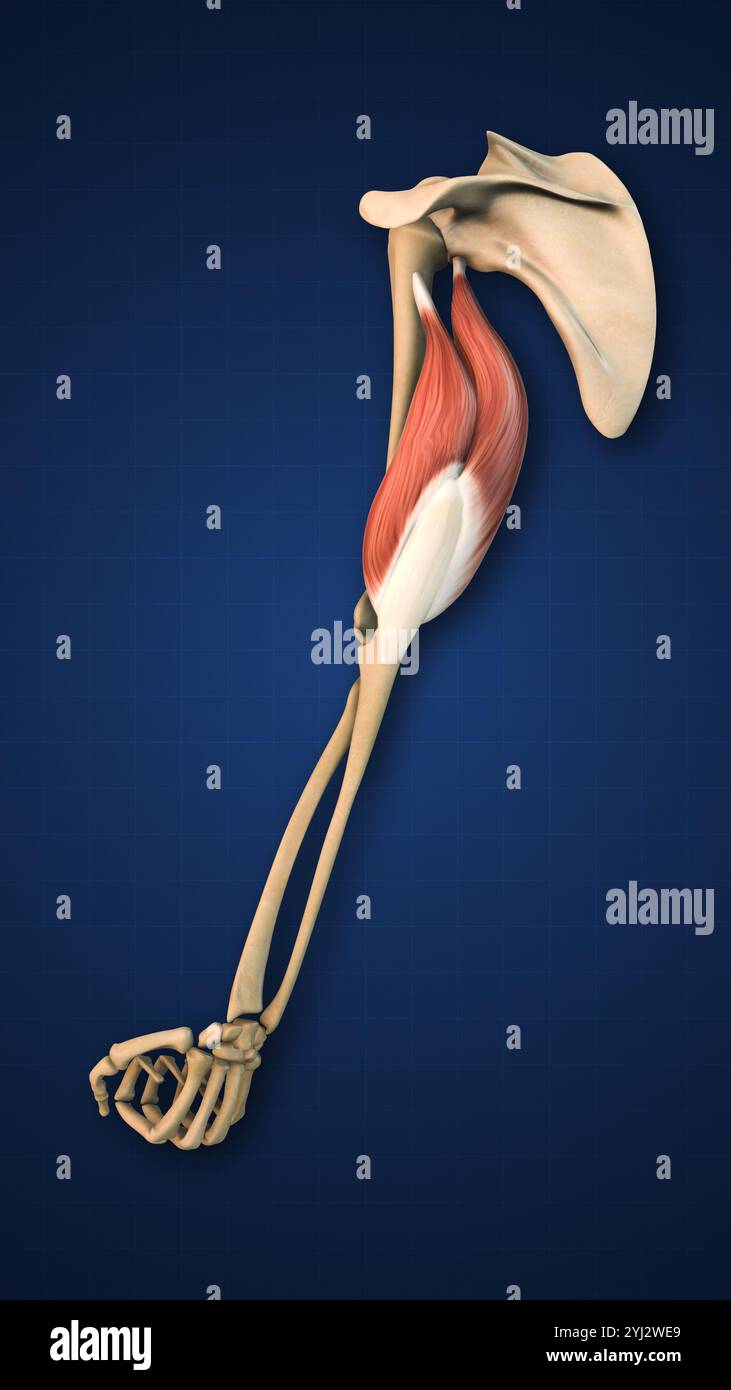

RF2JNYJM7–Präzise Knochen des Arms oder der oberen Extremität des menschlichen Skelettsystems oder Skeletts isoliert auf weißem Hintergrund 3D Rendering Illustration. Anterior und

RF2J8EXD1–Set Skelett Obere Extremitätenarme mit Schultergurt Human Vorderansicht der Rückseite mit teilweise transparenter Knochenposition. Hände, Schlüsselbein, Schulterblatt, Unterarme realistische flache Vektordarstellung der Anatomie

RF2K1XTCE–Anatomie des menschlichen Arms. Knochen und Gelenke von Arm, Unterarm und Hand. Vorderansicht des oberen Gliedes des Skeletts. Vektorgrafik

RF2JNYJM8–Genaue vordere oder vordere Ansicht der Knochen des Arms oder der oberen Extremitäten des menschlichen Skelettsystems isoliert auf weißem Hintergrund 3D Rendering Illustration. Ein

RF2JNYJMA–Genaue posteriore oder hintere Ansicht der Knochen des Arms oder der oberen Extremitäten des menschlichen Skelettsystems isoliert auf weißem Hintergrund 3D Rendering Illustration. Ein

RF3CM31GP–3D-Illustrationskonzept der Anatomie der Knochengelenke der oberen Extremitäten des menschlichen Skelettsystems

RF2JNYJM9–Genaue laterale oder Profilansicht der Knochen des Arms oder der oberen Extremitäten des menschlichen Skelettsystems isoliert auf weißem Hintergrund 3D Rendering Illustration. A

RF3CM2YY5–3D-Illustrationskonzept der Anatomie der Knochengelenke der oberen Extremitäten des menschlichen Skelettsystems

RF2JNYJJK–Genaue 3-Viertel-Vorderansicht oder Vorderansicht der Arm- oder oberen Extremitätenknochen des menschlichen Skelettsystems isoliert auf weißem Hintergrund 3D Rendering il